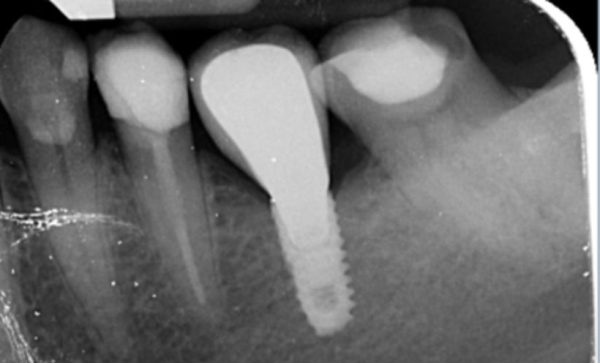

I have been a patient of Dr Verma for 8 years, my treatment has included crowns and an implant. Treatment plans and options are explained to me clearly, my concerns and anxieties are allieviated without hurry or pressure in a gentle and reassuring way. I feel my patient satisfaction is valued.

Sukal has been my dentist for many years, from simple check ups to a dental implant! I have always felt comfortable in the dentist chair and happily watched the TV on the ceiling while work is done on my teeth and never once felt any pain and always felt comfortable. I would never go anywhere else! Thank you all for being kind, caring and helpful at all times :-) Sarah Galloway